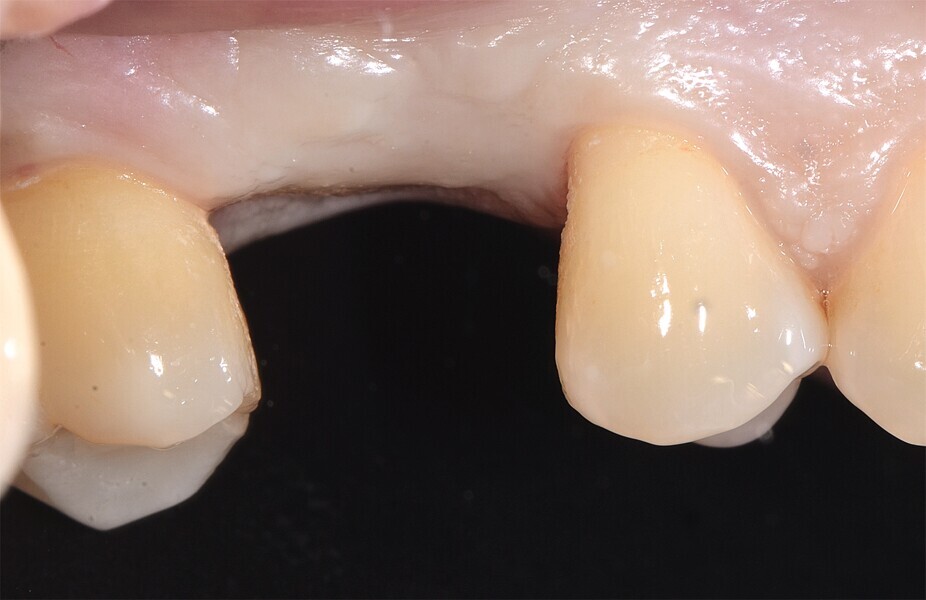

Fig. 55 : Intégration tissulaire et radiographie de contrôle à deux mois.

Fig. 56 : Intégration tissulaire et radiographie de contrôle à deux mois.

Le diagnostic a établi une atteinte de la furcation de la deuxième molaire supérieure, accompagnée d’un mauvais pronostic en raison d’une fissure inter-radiculaire. La dent a été extraite délicatement, de façon à conserver le septum inter-radiculaire dans le site où il était prévu de poser l’implant. La technique d’ostéodensification a été effectuée à l’aide de fraises Densah (Versah) et a permis d’obtenir une excellente stabilité de l’implant au niveau tissulaire. Une allo-greffe constituée d’un substitut osseux et un ciment au sulfate de calcium biphasique ont été utilisés pour préserver l’alvéole. Après huit semaines, nous pouvions constater et apprécier l’intégration parfaitement réussie de l’implant en céramique dans le tissu péri-implantaire (Figs. 46–56).